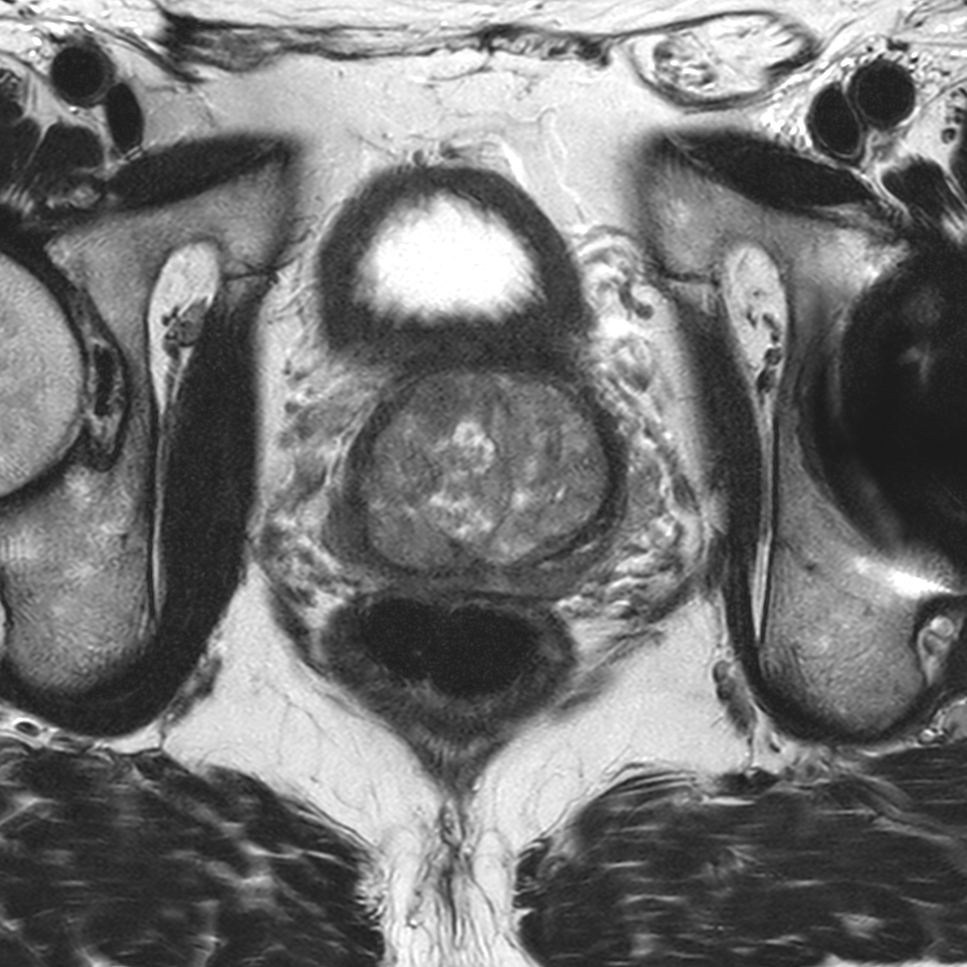

Coronal T2w TSE